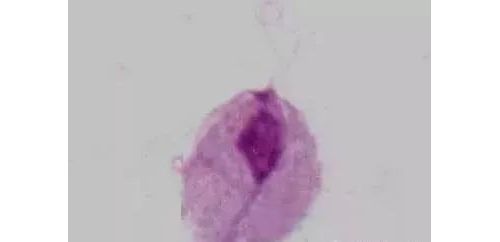

白带即阴道分泌物,指由女性生殖道不同部位的不同物质成分所组成的混合物,由液体和细胞组成。白带多沉积于后穹窿,呈酸性,阴道内 pH 保持在 4 ~ 4.5 之间。白带常规检查对确定阴道清洁度、发现病原体以及诊 ......